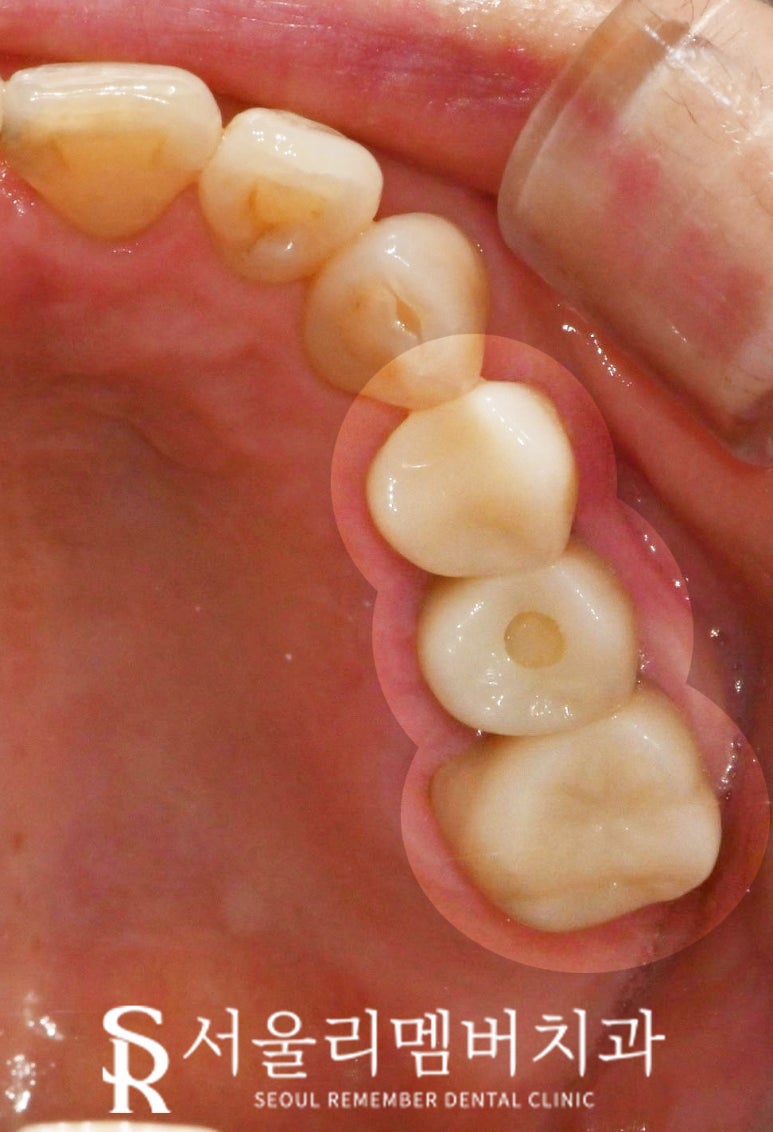

봉천역 치과 에서

마무리한 상악의 모습을 보시면

처음 제일 큰 고민이었던

왼쪽 위 치아 사이 공간은 모두 폐쇄되었고,

이제 더 이상 음식이 끼지 않으실 겁니다.

또한 아래로 정출되어

뿌리가 드러난 오른쪽 위 두 개의 어금니도

신경치료를 하고 브릿지로 씌워주었습니다.

그 결과 이제는 양쪽으로 모두

식사를 할 수 있게 되었기에

한두 개의 이가 저작력을

집중해서 버텨야 되는 문제도 사라졌고,

균등한 힘 분배를 통해

치주 질환이나 턱관절 장애도 예방할 수 있습니다.